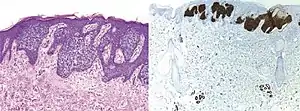

Comparison H&E stain (left) with BerEP4 immunohistochemistry staining (right) on a pathological section having BCC with squamous cell metaplasia. Only BCC cells are stained with BerEP4.[1]

BerEp4 has a high sensitivity and specificity in being positive only in BCC cells.[1] BerEp4 is normally negative in squamous epithelium and mesothelium, but otherwise normally positive most epithelial cells of the body.[3] It can also help in distinguishing pulmonary adenocarcinoma (positive BerEp4) from mesothelioma (generally negative BerEp4).[3][4]